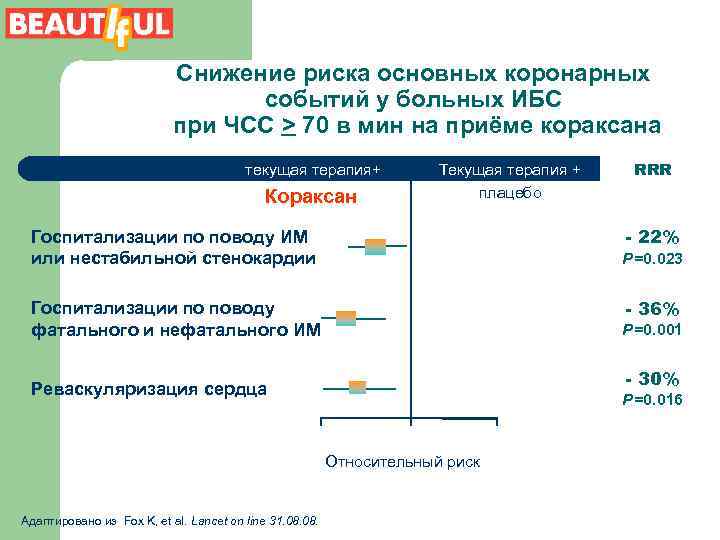

Исследование BEAUTI f FUL (2008) ЧСС > 70 уд/мин у больных ИБС – независимый новый ФР (предиктор ИМ и других сердечнососудистых осложнений)

Исследование BEAUTI f FUL (2008) Назначение кораксана больным стабильной стенокардией с дисфункцией ЛЖ и ЧСС > 70 в мин снижает повышенный риск развития ИМ на 36% и потребность в реваскуляризации на 30%.

Снижение риска основных коронарных событий у больных ИБС при ЧСС > 70 в мин на приёме кораксана текущая терапия+ Кораксан Текущая терапия + плацебо Госпитализации по поводу ИМ или нестабильной стенокардии Госпитализации по поводу фатального и нефатального ИМ RRR - 22% P =0. 023 - 36% P =0. 001 - 30% Реваскуляризация сердца P =0. 016 0. 5 1. 0 1. 5 Относительный риск Адаптировано из Fox K, et al. Lancet on line 31. 08.